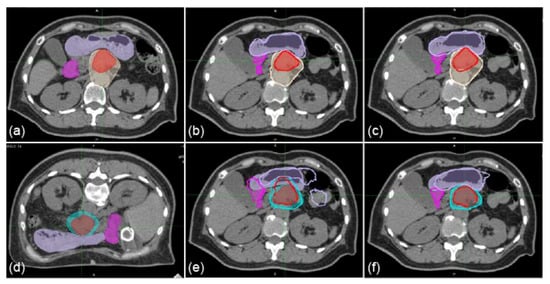

Figure 2. Sample axial images of supine and prone positions with the dose distributions of vertical beam fields. (a) 1st-IRCT images. (b,c) SP-PlanCT images. (d) 10th-IRCT images. (e,f) PR-PlanCT images. Filled red, beige, cyan, mauve, and magenta show delineations of GTV, CTV1, CTV2, stomach, and duodenum, respectively. Dose distributions are transferred from the 1st-IRCT images (a) to SP-PlanCT images with iDIR (b) and cDIR (c). Dose distributions are transferred from PR-PlanCT images (d) to SP-PlanCT images with iDIR (e) and cDIR (f).